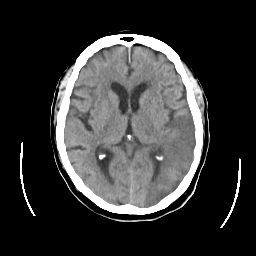

CT Study #2 -- Slice #14